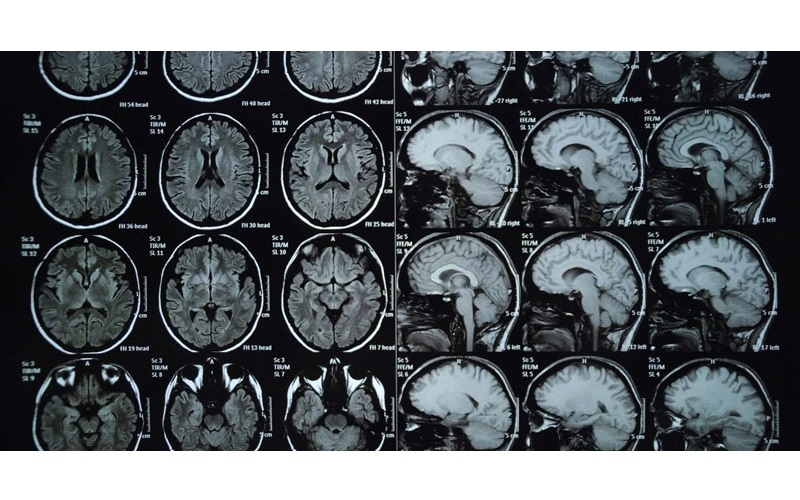

Chụp cộng hưởng từ (MRI) sọ não là một kỹ thuật hình ảnh tiên tiến, sử dụng từ trường và sóng radio để tái tạo hình ảnh chi tiết của não bộ và thân não mà không cần sử dụng bức xạ ion hóa. Nhờ tính an toàn, không xâm lấn, MRI được ứng dụng rộng rãi trong chẩn đoán các bệnh lý thần kinh.

Hệ thống máy MRI hoạt động dựa trên nguyên lý sử dụng một nam châm mạnh với đường hầm ở trung tâm. Khi chụp, người bệnh sẽ nằm trên bàn chụp và được đưa vào khu vực từ trường. Sóng radio sau đó tác động vào các nguyên tử hydro (H+) trong cơ thể, tạo ra tín hiệu được thu nhận bởi ăng-ten và chuyển đến máy tính. Hệ thống xử lý dữ liệu này sẽ tái tạo hình ảnh dưới dạng các lát cắt ngang của sọ não, đồng thời có thể dựng thành mô hình 3D giúp bác sĩ quan sát rõ ràng hơn các tổn thương và bất thường.

Chụp cộng hưởng từ (MRI) sọ não là một kỹ thuật hình ảnh tiên tiến